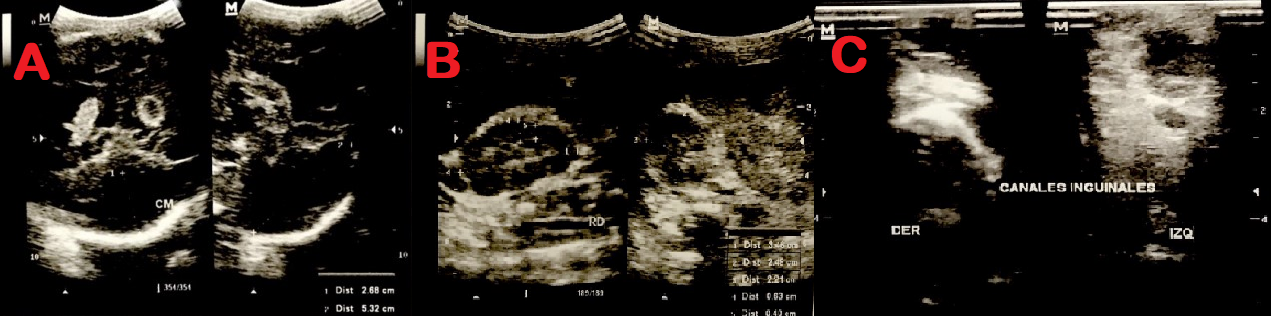

Figura 3. Ecografías.

A: presencia de quistes en la ecografía transfontanelar. B: ecografía renal pérdida de la relación cortico medular C: ecografía inguinal no es posible detectar testículos.

En la ecografía transfontanelar se aprecian las astas frontales, derecha de 4 mm e izquierda de 4.6 mm. Distancia tálamo occipital derecha de 9.8 mm, el izquierdo mide 15mm. Los plexos coroideos son irregulares, prominentes y lobulados. PCD de 9.8 mm, PCI de 9.8 mm con presencia de dos imágenes quísticas, una mide 5 mm y la mayor mide 13x9.6 mm sugestivas de quistes. La cisterna magna estaba aumentada de tamaño con dimensiones de 53 x 26 mm. Impresionaba como hipoplasia o agenesia del vermis cerebeloso acompañado de hipoplasia cerebelosa. La cortical presentaba surcos disminuidos, no se logró identificar cuerpo calloso (Ver figura 3).